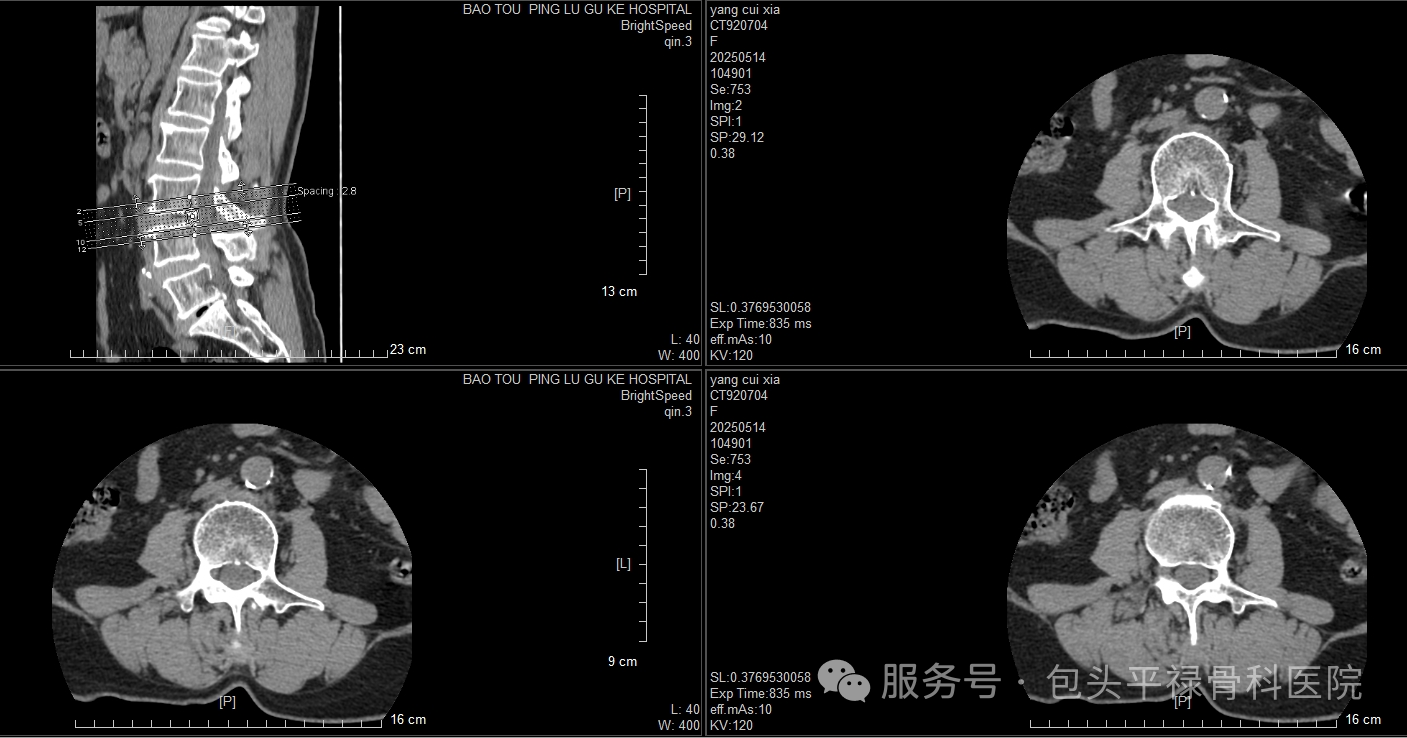

DR-CT-MRI影像对比

图源:包头平禄骨科医院

CT,即计算机断层扫描,利用X射线对人体部位进行断层扫描,再通过计算机处理后二次成像,提供人体被检查部位的完整三维信息,可使器官和结构清楚显影。可以把CT检查比喻成面包切片,把人体拍成许多的“薄片”,然后医生一片片仔细观察,可以拍出人体内部的更多细节,帮助医生得出更精确的诊断。

全身部位均可进行CT平扫,包括头颅、胸腹部、脊柱、盆腔、四肢等部位,对于骨科来说,CT检查更多应用于对骨性问题的评估,比如关节内骨折碎成几块,每一块的位置形态、脊柱有没有韧带的骨化或严重骨折的相对位置信息等,对医生制订诊疗方案有重要的指导作用。

优点:图像分辨率高、成像清晰、扫描速度快、适用范围广,有些特殊部位的细微骨折、骨肿瘤、骨结核,CT具独特的优势。

缺点:辐射量略高、费用略高、增强CT显影剂有致敏风险。